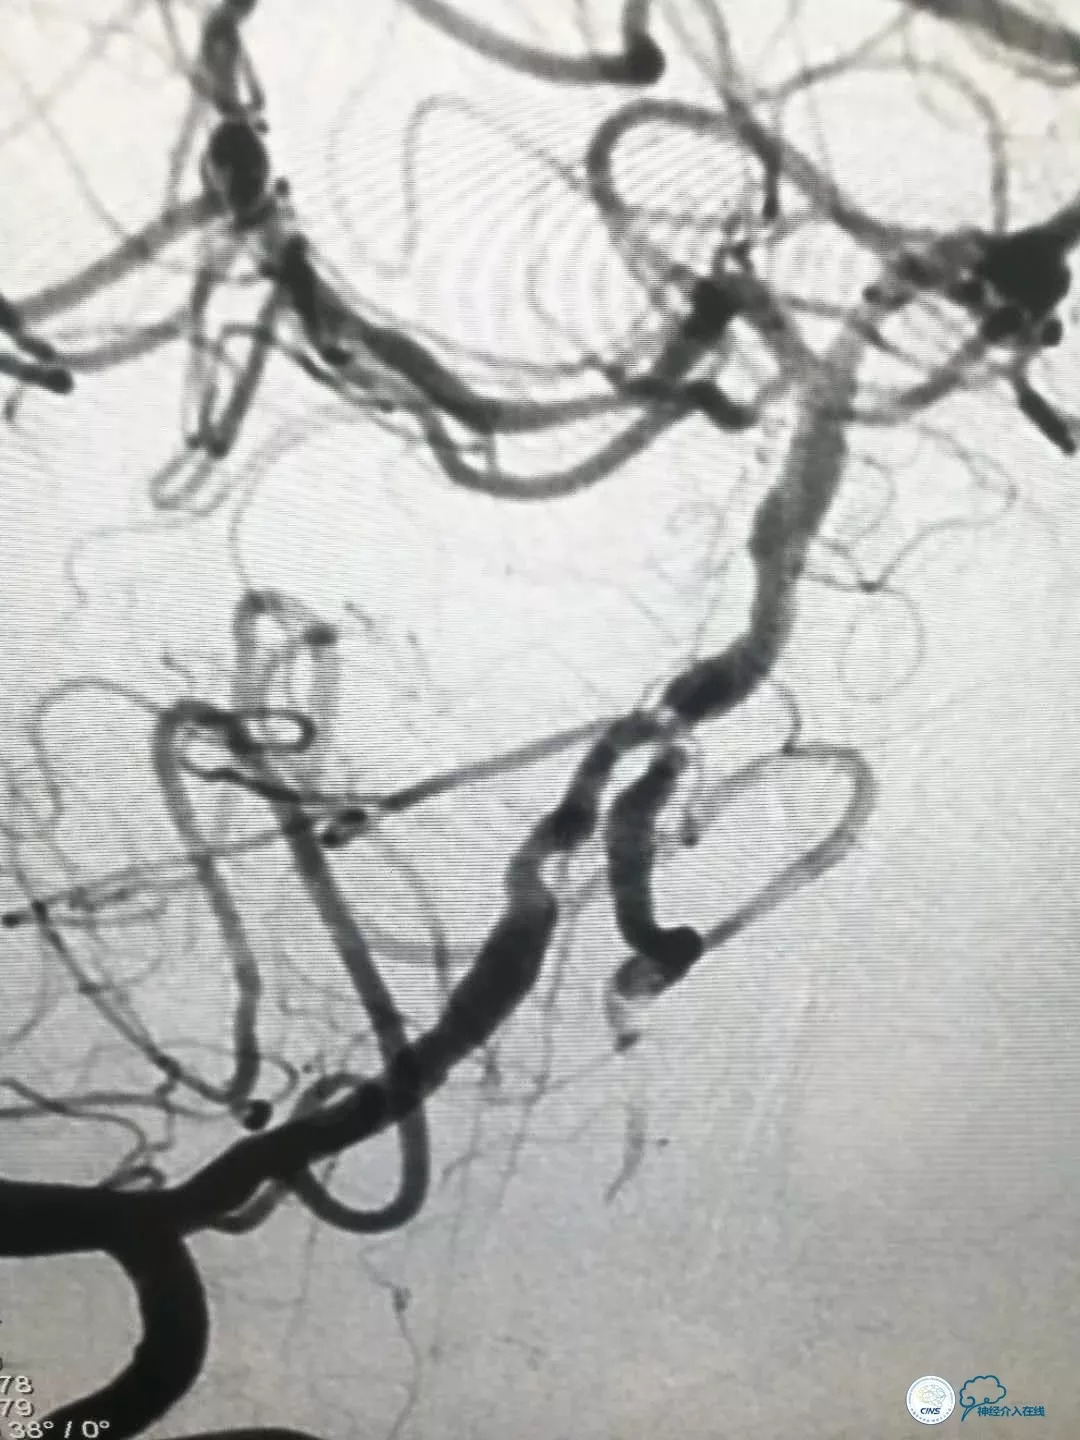

DSA提示: 右椎动脉V4段及基底动脉近端串联重度狭窄,左椎动脉开口迂曲,左椎动脉V4段重度狭窄,发出PICA后以远显影浅淡,左颈内动脉后交通段动脉瘤(2×2.5mm)(图4-8)。

图4

图5

图6

图7

图8